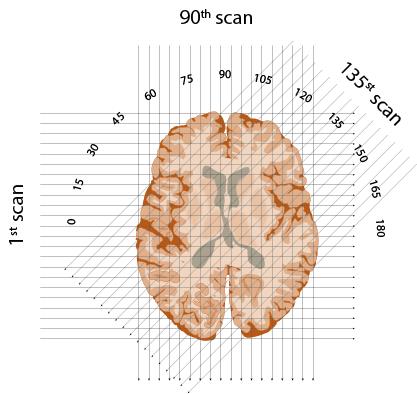

X-rays beam through each 'slice' of brain, oriented at each degree from 1 to 180 in a semicircle. Edmund S. Higgins, CC BY-ND

First, he would conceptually divide the brain into consecutive slices – like a loaf of bread. Then he planned to beam a series of X-rays through each layer, repeating this for each degree of a half-circle. The strength of each beam would be captured on the opposite side of the brain – with stronger beams indicating they'd traveled through less dense material.